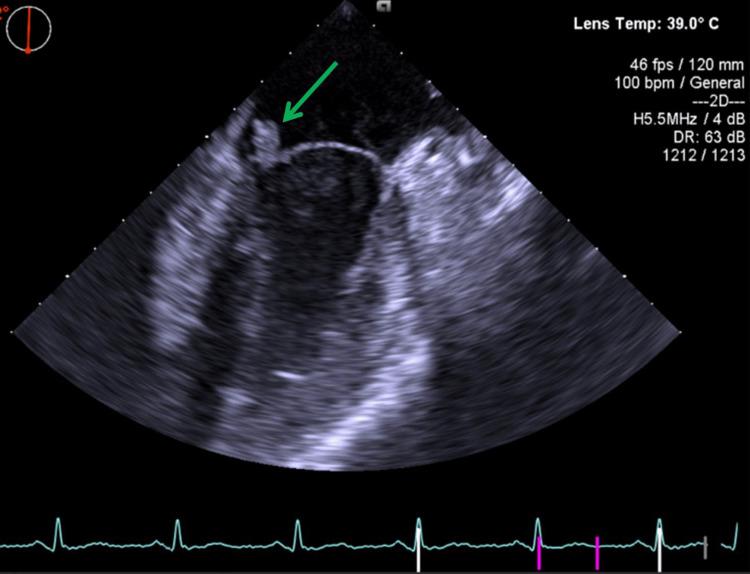

Infective endocarditis (IE) is a rare but serious life-threatening disease, often presenting with highly variable clinical symptoms. Risk factors for this condition include valvular heart disease, age, medical procedures, dental procedures, and intravenous drug use. Patients with IE may exhibit valve dysfunction, heart failure, or neurological complications such as stroke, the latter being caused by an embolus originating from valvular vegetations that occlude more distal vessels in the cerebral circulation. Diagnosis is based on the modified Duke criteria. We report a case of a 20-year-old male patient who presented to the emergency department with the acute onset of aphasia, right-sided hemiparesis, and fever. Neurological examination revealed a National Institute of Health Stroke Scale score of 10, and computed tomography (CT) angiography confirmed a left middle cerebral artery occlusion. Since endocarditis was not known at the time of stroke diagnosis, the patient underwent thrombolysis. He then underwent thrombectomy with successful recanalization, and the retrieved thrombus was sent for microbiological analysis. Laboratory findings showed leukocytosis, elevated erythrocyte sedimentation rate, and elevated C-reactive protein, and both blood and thrombus cultures were positive for . An echocardiogram revealed a vegetation in the mitral valve, confirming the diagnosis of IE. The patient was treated with ceftriaxone, rifampicin, and gentamicin according to antibiotic susceptibility results, and underwent mitral valve replacement surgery, demonstrating a good clinical outcome with recovery from the neurological deficits. This case highlights the importance of considering the diagnosis of IE in patients presenting with stroke and fever, as ischemic stroke can be an embolic complication of IE. It also emphasizes the potential role of microbiological analysis of clots retrieved through thrombectomy in identifying the infective agent, especially in patients where blood cultures are negative or inconclusive. Such identification might help select appropriate antibiotic therapy, although more studies are required to better define its role in patient care.

感染性心内膜炎(IE)是一种罕见但严重的危及生命的疾病,通常表现出高度可变的临床症状。该疾病的危险因素包括瓣膜性心脏病、年龄、医疗操作、牙科操作和静脉药物使用。IE患者可能出现瓣膜功能障碍、心力衰竭或神经系统并发症,如中风,后者是由源自瓣膜赘生物的栓子引起的,该栓子会阻塞脑循环中更远端的血管。诊断基于改良的杜克标准。我们报告一例20岁男性患者,他因急性失语、右侧偏瘫和发热就诊于急诊科。神经系统检查显示美国国立卫生研究院卒中量表评分为10分,计算机断层扫描(CT)血管造影证实左大脑中动脉闭塞。由于在中风诊断时未知患有心内膜炎,该患者接受了溶栓治疗。然后他接受了血栓切除术,血管成功再通,取出的血栓送去进行微生物分析。实验室检查结果显示白细胞增多、红细胞沉降率升高和C反应蛋白升高,血液和血栓培养均对 呈阳性。超声心动图显示二尖瓣有赘生物,证实了IE的诊断。根据抗生素敏感性结果,该患者接受了头孢曲松、利福平和庆大霉素治疗,并接受了二尖瓣置换手术,临床结果良好,神经功能缺损得以恢复。该病例强调了在出现中风和发热的患者中考虑IE诊断的重要性,因为缺血性中风可能是IE的栓塞并发症。它还强调了对通过血栓切除术取出的凝块进行微生物分析在识别感染病原体方面的潜在作用,特别是在血培养阴性或不确定的患者中。尽管需要更多研究来更好地确定其在患者护理中的作用,但这种识别可能有助于选择合适的抗生素治疗。